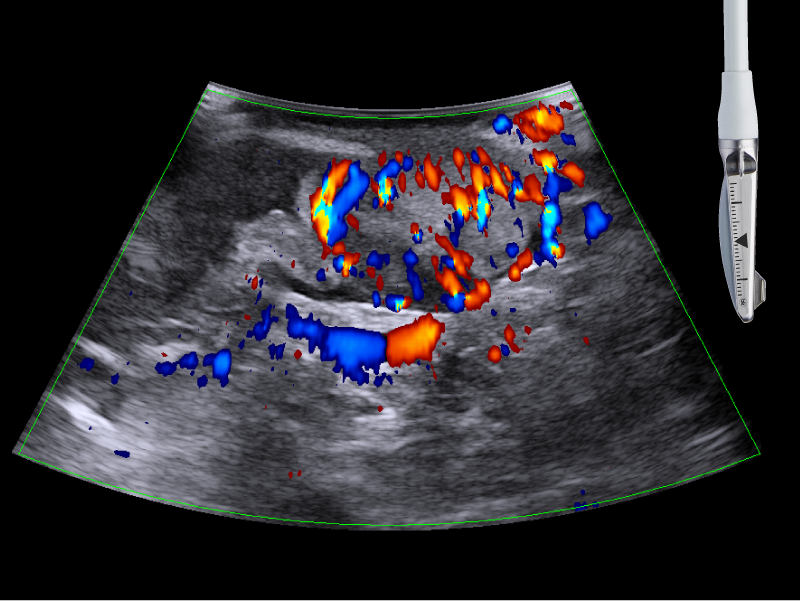

Visualize hepatic and pancreatic tumors and guide needle placements

Active imaging supports liver and pancreas ablation procedures by helping you visualize lesions and blood vessels, identify healthy tissue vs. tumor, and guide and view needle placements.